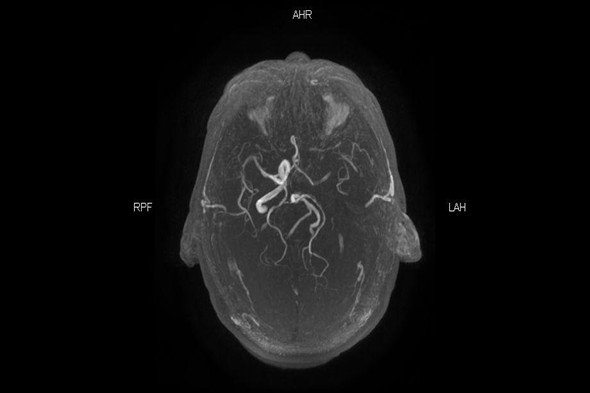

介入科刘琳团队接到通知立即启动脑卒中快速通道,患者准备MR检查的同时介入导管室护士、急诊麻醉师刘洋、赵亮已到位。核磁科崔红升主任团队经过详细的检查分析评估,得出结果为左颈内动脉起始栓塞,颅内小梗塞病灶显影,还有大量可挽救的脑细胞,适合介入取栓治疗挽救患者生命。

MR 左颈内动脉未显影

MR 血管重建左颈内动脉消失,右颈内动脉显影正常